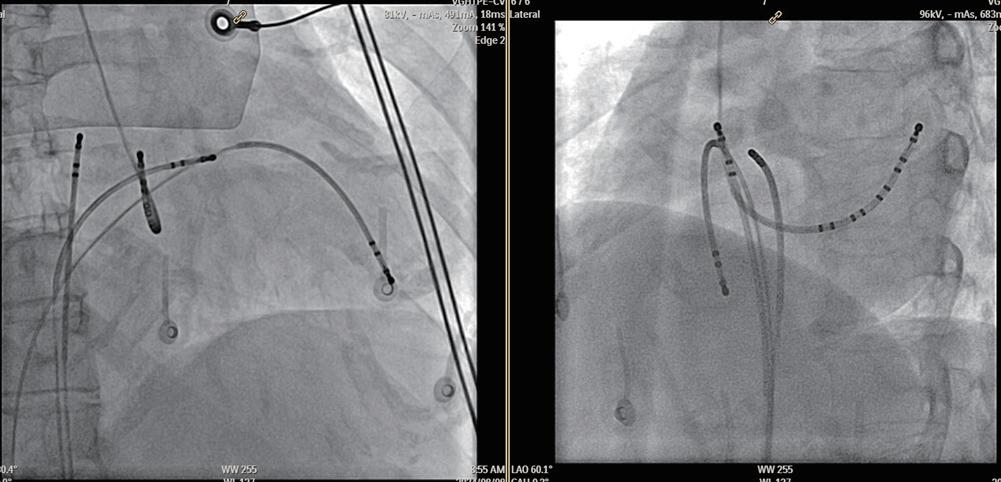

進行首次 AF 消融的患者通常在心臟內超音波 (Intracardiac echocardiography, 簡稱ICE)和X光透視引導 下兩根十極導管在ICE和透視引導下放置,其中一根位 於冠狀靜脈(CS),另一根放置在crista terminalis(CT)上( 最遠端電極延伸至上腔靜脈),以促進non-PV trigger的 明確區域化。之後進行兩次 transseptal puncture ,使多 電極 mapping catheter 和接觸力感測灌流消融導管進入 左心房。在全身麻醉下,患者進行 electroanatomical mapping(EAM),隨後對肺靜脈進行環狀隔離術(PVI)。 在確認PV entrance and exit block後,把多電極mapping catheter 會放置於後壁,消融導管置於左上肺靜脈內, 進行有明確定義的誘發性動作,以識別non-PV trigger。

(圖三) 診斷管放置的位置